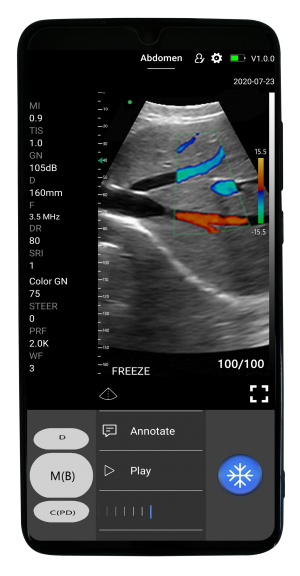

El escáner también destaca por su compatibilidad con telemedicina gracias a la capacidad de transmisión de datos en tiempo real desde dispositivos inteligentes. Con software gratuito de por vida y fácil actualización, este equipo ofrece una solución integral, moderna y altamente rentable para profesionales de la salud que necesitan movilidad y precisión diagnóstica.

| Modo de escaneo | B, B/M, Color, PW |

Fácil de usar

En iOS y Android

- Puedes hacerlo fácilmente, incluso si no eres un profesional de la ecografía. Solo sigue estos pasos:

- Comience a escanear dentro de 1 segundo después de encender el escáner de ultrasonido portátil y ejecutar la aplicación MicroVue.

- Elija entre los ajustes preestablecidos con IA para realizar ajustes instantáneos y obtener una buena imagen. Escanear con el escáner SonoHealth es como usar la aplicación de cámara de su teléfono.

- Deslice el dedo hacia la izquierda y hacia la derecha para cambiar los modos de escaneo, la ganancia, deslícese hacia arriba y hacia abajo para cambiar la profundidad y más.

Condensamos la unidad principal en una pequeña placa de circuito incorporada en la sonda, pequeña y liviana, y que muestra la imagen en la aplicación instalada en el teléfono inteligente/tableta a través de Wifi (wifi interno de la sonda, no necesita señal Wifi externa) o transferencia USB.

Aplicaciones

-

Abdomen

-

Cardíaco

-

Pulmonar

-

Vascular

-

Obstetricia

-

Emergencias (POCT)